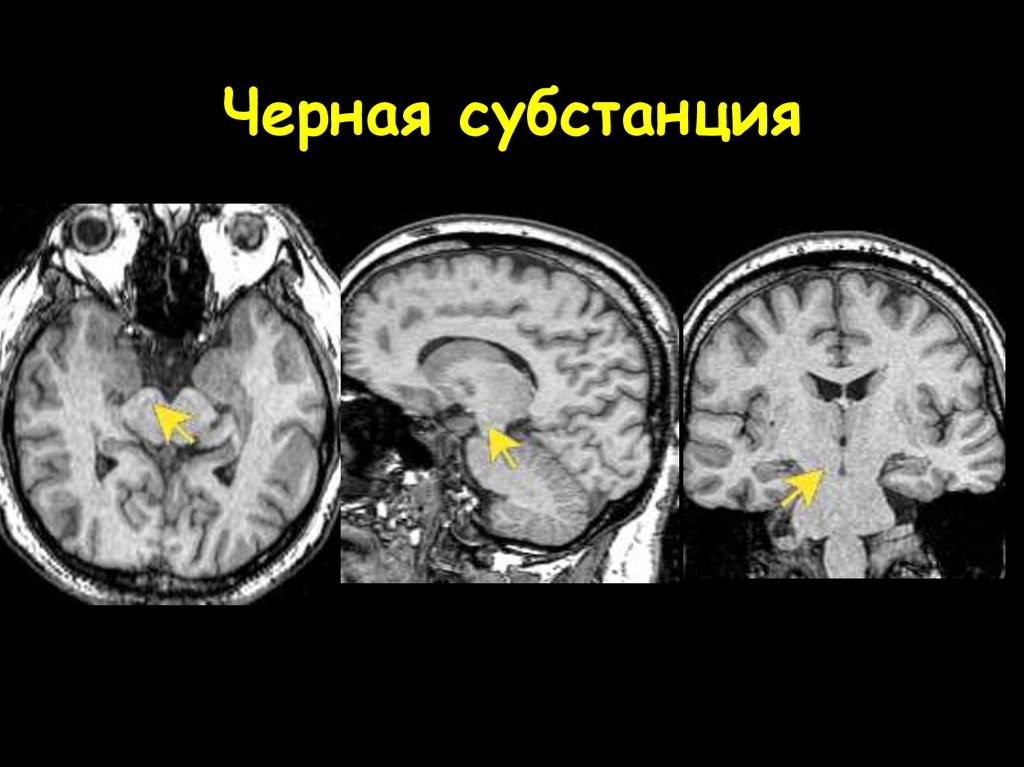

2.2. Анатомия чёрной субстанции

Субстанция является одной из древнейших частей в структуре мозга, расположенная в его сердцевине – четверохолмии среднего мозга. Исторически она отвечала за движения наших предков, затем, когда они усложнились, изменилось и строение. Черное вещество обрастало нервными связями, формируя более сложную структуру.

Рис. 8. Расположение чёрной субстанции (рисунок из интернета)

Название чёрное вещество получило благодаря действию пигмента – нейромеланина, окрашивающего клетки в тёмный цвет. Чёрное вещество среднего мозга неоднородно, оно разделено на две половинки: правую и левую. Кроме того, в субстанции выделяют два слоя: вентральный и компактный. Вентральный находится ближе к передней части головы, а компактный – к задней. Первый обеспечивает синтез нейромедиатора дофамина, второй – занимается переработкой поступающей информации и передачей её в другие структуры. УЗИ чёрной субстанции головного мозга показывает, что она связана со всеми отделами, но наиболее тесно – с базальными ганглиями и зрительными буграми.

В 1910 году в ней выделили две части: pars compacta и pars reticulata. Первая косвенно управляет движением (электрическая стимуляция не приводит к действиям), а вторая служит важным процессовым центром в базальных ганглиях. Гибель дофаминергических нейронов в pars compacta – один из симптомов болезни Паркинсона, из-за чего у больных развиваются нарушения в движениях.